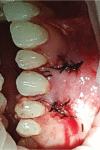

Gingival recession is an oral health problem that affects a large part of the population. Several treatments are suggested in the current literature; among them is the use of buccal fat pad grafting. The objective of this case report is to describe the treatment of a Miller Class I gingival recession using a nonpedicled buccal fat pad graft immediately after performing the surgery for buccal fat pad removal (bichectomy technique). First, bilateral surgical removal of the buccal fat pad was performed with the main objective of eliminating oral mucosa biting. The recipient site was prepared to receive a portion of the fat pad that was cut and macerated in a size that was sufficient to cover the recession. The patient was followed up at 15, 30, 60, and 365 days postsurgery, and the results showed an elimination of the oral mucosa biting and complete coverage of the gingival recession. It was concluded that the nonpedicled buccal fat pad graft is another option for the treatment of Miller Class I recessions.